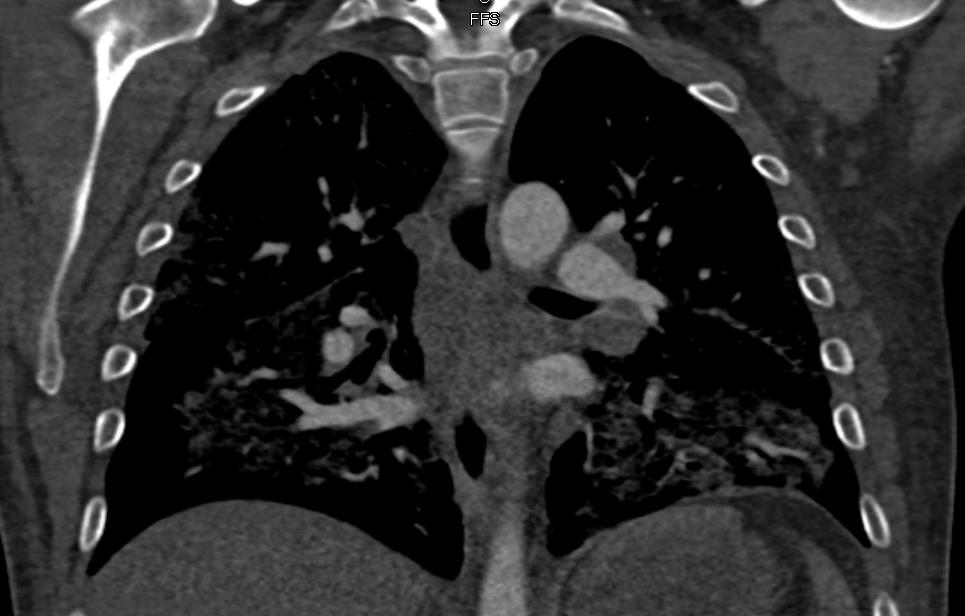

Infectious disease recommended broad-spectrum antibiotic coverage with vancomycin, clindamycin, piperacillin-tazobactam, and levofloxacin due to concern for Aeromonas species from freshwater exposure. Unexpectedly on postop day 3, the patient started complaining of respiratory discomfort and overall body swelling. The patient had new-onset dyspnea, hypoxemia, hydrocele, and edema, resulting in placement on a BiPAP machine. Laboratory investigation revealed leukocytosis, with a white blood cell count of 19.1×109/L (normal range 4×109/L to 11×109/L) with normal peripheral absolute eosinophil count of 0×109/L, and lactate level of 0.9 mmol/L. His arterial blood gas pH was 7.48 (normal pH 7.35 to 7.45), partial pressure of O2 77 mmHg (normal greater than 70-125 mmHg), partial pressure of carbon dioxide 26 mmHg (normal 35 mmHg to 45 mmHg), and calculated bicarbonate of 22 mmol/L (normal 23 mmol/L to 28 mmol/L). A repeat chest X-ray (see image to left) revealed new onset of pulmonary edema. A new computed tomography (CT) of the chest (see image below) showed diffuse ground-glass opacities with small pleural effusions and diffuse subpleural sparing, attributable to pulmonary edema with possible pneumonitis.